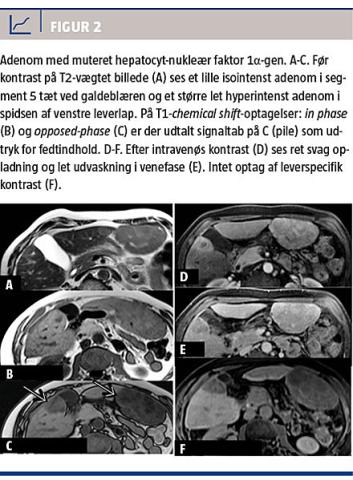

Ved MR-skanning før kontrast er adenomer iso- eller hyperintense på T2-vægtede billeder, og på T1-vægtede billeder kan de have alle signalintensiteter afhængigt af indhold af fedt, blødning og nekrose [19]. De udviser forskellige opladningsmønstre, og en analyse af signalintensitet og opladningsmønster muliggør differentiering mellem forskellige undertyper: inflammatoriske adenomer (Figur 1) har et højt T2-signal med endnu højere signal i tumorperiferien, forårsaget af dilaterede sinusoider. På T1-vægtede billeder er de iso- eller lethyperintense, de er uændrede ved chemical shift-optagelser, da de ikke indeholder fedt og har kraftig arteriel opladning, som persisterer i venefase og sen fase.

Adenomer med muteret HNF1α-gen (Figur 2) er

iso- eller lethyperintense på T2-vægtede billeder og iso- eller hyperintense på T1-vægtede billeder med diffust signaltab på chemical shift-optagelser pga. intracellulær steatose. De ses ofte i en diffust steatotisk lever og har moderat opladning i arteriefase, ingen persisterende opladning i senere faser, men vender hurtigt tilbage til udseendet før kontrastindgift [12, 22].

β-cateninaktiverede og uklassificerbare adenomer har ikke et specifikt udseende på en MR-skanning, men de indeholder ikke fedt, har oftest kraftig arteriel opladning med eller uden udvaskning og kan ligne HCC [22]. Vha. MR-skanning kan man således skelne de fedtholdige adenomer med muteret HNF1α-gen fra de øvrige typer. Fælles for alle adenomtyper er, at de i modsætning til FNH ikke indeholder galdeveje og derfor ikke optager hepatobiliær, leverspecifik MR-kontrast. Det gælder både for gadobenatdimeglumin, som er et gadoliniumkelat, hvor 5% af kontrasten optages i levercellerne og udskilles i galdevejene 1-3 timer efter indgift [23], og for gadoxetat, hvor op til 50% af kontrasten optages i levercellerne og udskilles i galdevejene efter 15 minutter [24].